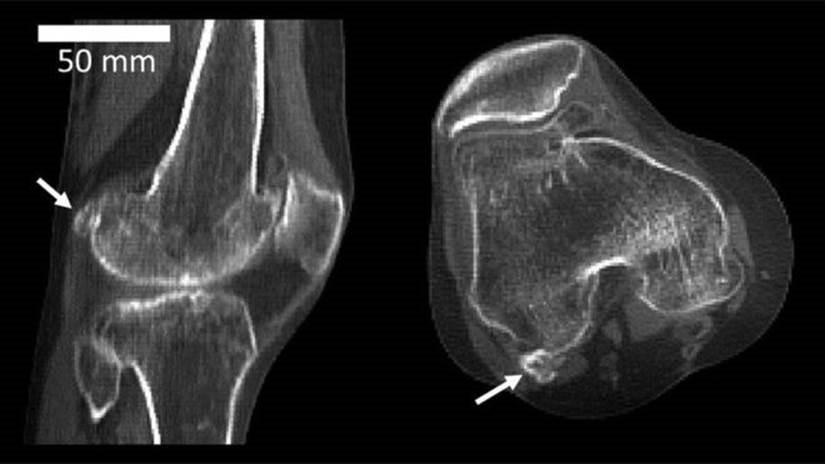

A fabela estava presente em 11% da população mundial em 1918 e subiu para 39% em 2018; sua função ainda é um mistério para a ciência. A seta indica onde está a fabela, atrás do joelho

A fabela é encontrada, em algumas pessoas, na área do tendão que fica atrás do joelho.

Segundo a análise dos cientistas, em 1918 a fabela estava presente em 11% da população mundial. Em 2018, essa proporção passou para 39%.

A fabela é encontrada atrás da rótula